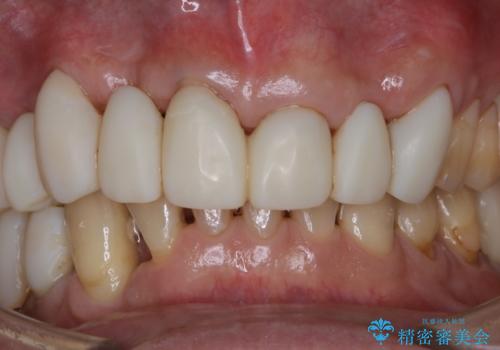

- 治療中のメンテナンス希望の方です。PMTC30分コースを行いました。

PMTCとはプロフェッショナル・メカニカル・トゥース・クリーニングの略です。

専門的な機械や器具を使用して歯のクリーニングを行います。

口の中には、目には見えない細菌がたくさんいます。歯周病は細菌による感染症です。歯面のプラークや着色(ステイン)など、細菌をしっかり除去し、治療の妨げにならないよう、治療中にPMTCを行うことも大切です。